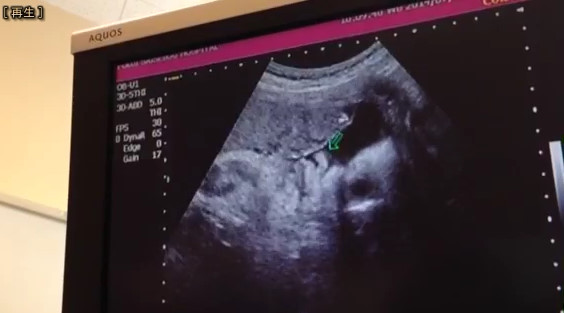

検診でした、前回からドップラー始まりました、、どきどき

まばたきしてました、分かりますか

こんな感じ

なんか鼻べちゃな気がするんだけど、気のせいか?

鼻が一番親子似る部分だと思うんだけど、、、、

べちゃってないか、狭いからなだけか?